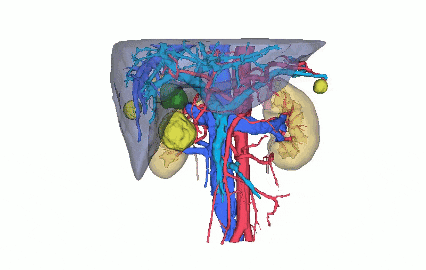

术前阿梵D——泌尿系统三维重建结果

三维重建泌尿系统动静脉预览

三维重建泌尿系统整体预览